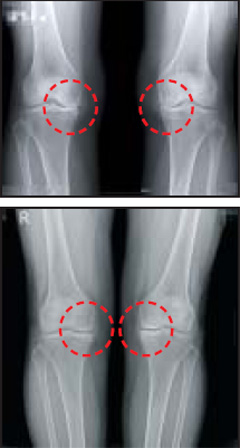

줄기세포 치료 전 환자의 무릎 엑스레이 사진(위)과 수술 1년 후 엑스레이 사진. 수술 전 맞닿아 있던 무릎뼈가 연골이 자라면서 사이가 떨어졌다. / 연세사랑병원 제공

지방조직에서 줄기세포를 추출해 이식하는 자가지방 줄기세포치료도 연구가 활발하다. 2012년 지방에서 뽑은 줄기세포가 관절염 치료에 효과가 있다는 연구결과가 보건복지부 지정 관절전문병원인 연세사랑병원에서 세계 최초로 발표됐다. 최근에는 지방조직에서 추출한 줄기세포가 65세 이상 노인들에게도 효과적이라는 연구결과도 이 병원에서 나왔다. 인공관절수술을 받아야 하지만 수술 두려움으로 수술을 거부했던 65세 이상 환자 30명(평균 나이 70.3세)에게 환자의 지방조직에서 추출한 줄기세포를 이식했더니 이들의 통증수치가 수술 전 4.7(5점 만점)에서 수술 후 1.7로 줄었으며 23명의 환자가 매우 만족한다는 내용이다. 시술 1년 후 관절내시경 검사에서 환자의 62%가 손상된 연골이 회복됐고 2년 동안 연골손상이 더 이상 진행되지 않은 환자는 87.5%였다. 이 연구결과는 지난해 12월 유럽 슬관절및스포츠학회 공식학술지에 게재됐다. 고용곤 원장은 "수술 이외에 다른 방법이 없지만 수술 자체를 부담스러워하던 고령 환자들도 자가지방 줄기세포를 이용한 치료가 효과적인 대안이 될 수 있다는 뜻"이라고 말했다.